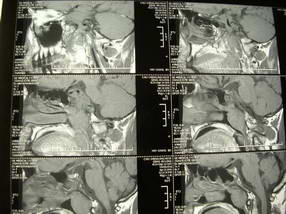

扫描示鼻咽腔不对称,中度狭窄,右侧咽隐窝消失,局部软组织肿块,鼻咽右侧壁增厚形成肿块,突入鼻咽腔,肿块平扫呈等密度,肿块向深部侵润,右侧翼内外肌受侵,右侧咽旁间隙变窄;向后生长,头长肌界线欠清,向后上生长侵犯同侧颈动脉鞘区。双侧海绵窦增宽,内见软组织影与鼻咽部肿块相连。考虑鼻咽癌。鼻咽癌主要是放射治疗,且效果较好;到当地有治疗设备较大医院治疗即可。

鼻咽部新生物(纤维血管瘤?鼻咽癌?)侵犯右侧中颅窝底及右侧海绵窦;建议必要时活检定性。

鼻咽部新生物侵犯右侧中颅窝底及右侧海绵窦,鼻咽癌可能性大。建议增强扫描。纤维血管瘤禁忌穿刺。

典型鼻咽癌侵犯右侧海绵窦(对放疗敏感)